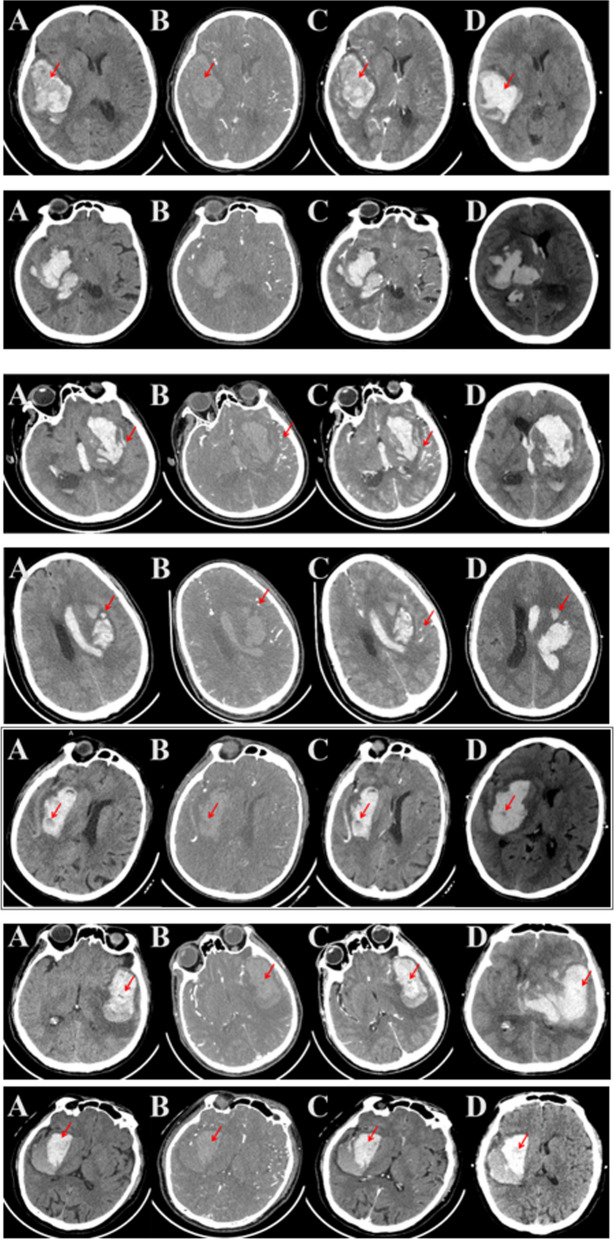

A total of 62 patients (16.9%) presented with hematoma expansion (HE) on a follow-up NCCT scan. Among the observed NCCT signs, the following frequencies were noted: "heterogeneous density" in 168 cases (37.3%), "irregular shape" in 216 cases (47.9%), "island sign" in 95 cases (21.1%), "satellite sign" in 117 cases (25.9%), "swirl sign" in 167 cases (37.0%), "black hole sign" in 50 cases (11.1%), and "blend sign" in 87 cases (19.3%). The distribution of NCCT signs within 24 h post-onset between patients with poor and good prognoses is provided in Table 1. The representative imaging pictures of NCCT scan were shown in Fig. 2.

Fig. 2.

Representative imaging pictures of CT scan. From top to bottom was Homogenous density, Irregular shape, Island sign, Satellite sign, Swirl sign, Black hole sign, Blend sign. A Plain CT scan; B CT enhancement; C Sequential CT plain scan; D Reexamination CT scan in 24 h. The arrow represented the signs position